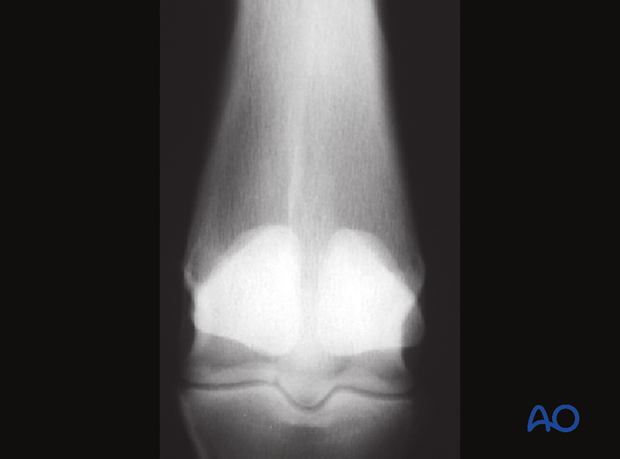

Left: This conservatively treated medial condylar fracture healed radiographically over most of its length but some radiolucency can still be seen near the joint at 6 months post-injury.